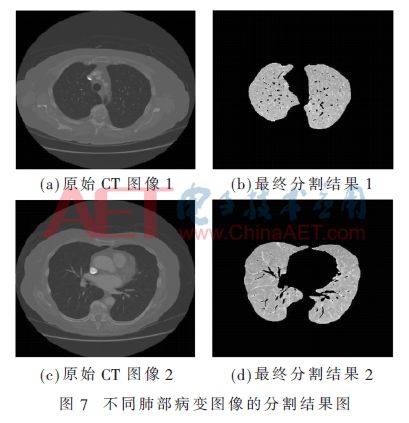

为了对两种方法融合后对图像分割效果的可行性进行验证性分析,进一步列出两组不同类型的肺部病变图像的分割结果,如图7所示。

从分割结果来看,本文提出的方法能够精准、全面地提取肺实质区域,相较于单独使用区域生长法,显著解决了边界漏检的问题。通过融合水平集法的精确分割技术,该方法不仅能够清晰地观察到肺实质内部的细节信息,还能更精确地定位肺部的边缘信息,同时有效避免了图像过分割的问题。此外,该方法对于多种类型病变的肺部图像具有良好的适应性,为后续的图像分析和处理提供了可靠的技术基础。